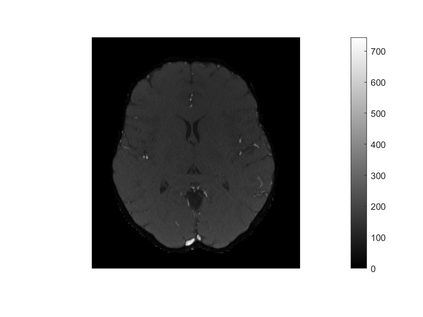

One of the most prominent methods for uncertainty quantification in high-dimen-sional statistics is the desparsified LASSO that relies on unconstrained $\ell_1$-minimization. The majority of initial works focused on real (sub-)Gaussian designs. However, in many applications, such as magnetic resonance imaging (MRI), the measurement process possesses a certain structure due to the nature of the problem. The measurement operator in MRI can be described by a subsampled Fourier matrix. The purpose of this work is to extend the uncertainty quantification process using the desparsified LASSO to design matrices originating from a bounded orthonormal system, which naturally generalizes the subsampled Fourier case and also allows for the treatment of the case where the sparsity basis is not the standard basis. In particular we construct honest confidence intervals for every pixel of an MR image that is sparse in the standard basis provided the number of measurements satisfies $n \gtrsim\max\{ s\log^2 s\log p, s \log^2 p \}$ or that is sparse with respect to the Haar Wavelet basis provided a slightly larger number of measurements.